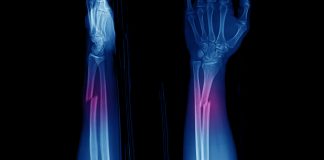

Tag: fratture ossee